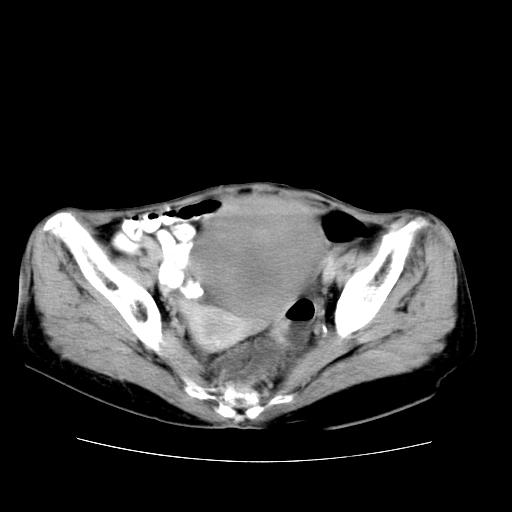

女性,72岁。

主诉下腹部坠痛不适1年余。

子宫增大如孕3月大小,质软,活动可,无压痛。

b超提示:盆腔(子宫前方)低回声团块。

临床诊断:盆腔肿块查。

1、这个肿瘤密度均匀,增强后轻中度均匀性强化,与左侧附件关系密切,肿瘤边缘光整、清晰。

2、左侧卵巢增大呈8×8×10cm大小,实性,表面光滑,边清,左侧输卵管爬行于左卵巢上,子宫萎缩。右输卵管、卵巢萎缩。

左侧卵巢纤维瘤(性索间质肿瘤)

卵巢纤维瘤为良性卵巢性索间质肿瘤,常为单侧发病,当合并腹水或胸腹水时称麦格斯(meigs)综合征,肿瘤切除后胸腹水可消失。ct表现为盆腔内边界清楚的圆形或椭圆形肿块,常有分叶或不规则;肿瘤多为实性,少数为囊性、囊实性,完全囊性者可见壁结节。实性部分与子宫等密度;增强扫描常为轻度强化或几乎不强化。